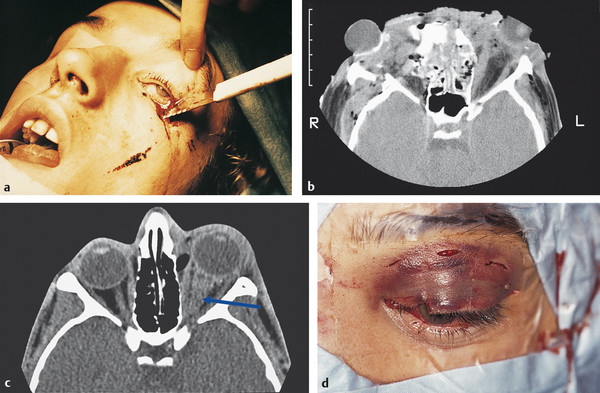

Penetrating orbital trauma (Fig. 29‑1a).

Partial or complete avulsion (Fig. 29‑1b).

Intraoptic nerve sheath hematoma (Fig. 29‑1c,d).